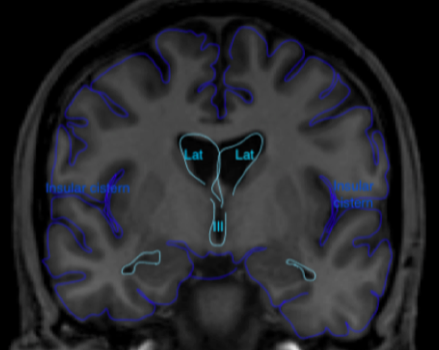

As a medical student the first thing about the brain I knew by heart was the ventricular system. It was so easy to remember: *Cerebrospinal fluid (CSF) gets produced by the choroid plexus in the lateral ventricles -> flows via the foramen of Monro to the 3rd ventricle -> from the 3rd ventricle via the aqueduct to the 4rd ventricle and then via L-Lateral foramina of Luschka and a M-Median foramen of Magendie to the subarachnoid space. *Granulations of Pacchioni in the subarachnoid space resorb CSF.

Figure 1 Coronal (above) and sagittal (below) T1 weighted images showing the lateral ventricles (lat), third (III) and fourth ventricle (IV) and several subarachnoid cisterns. The temporal horn of the lateral ventricle is anatomically close to the subarachnoid space, more specific the choroid fissure.